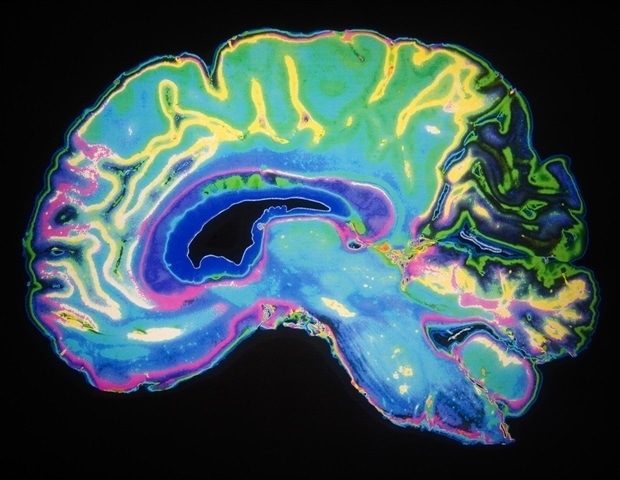

‘There’s no reason to ban us from playing’: Analysis debunks notion that transgender women have inherent physical advantages in sports

Science

Really Simple SyndicationFebruary 7, 2026

A meta-analysis of 52 studies that included over 5,000 transgender people suggests that transgender women’s physical fitness after hormone therapy is comparable to that of